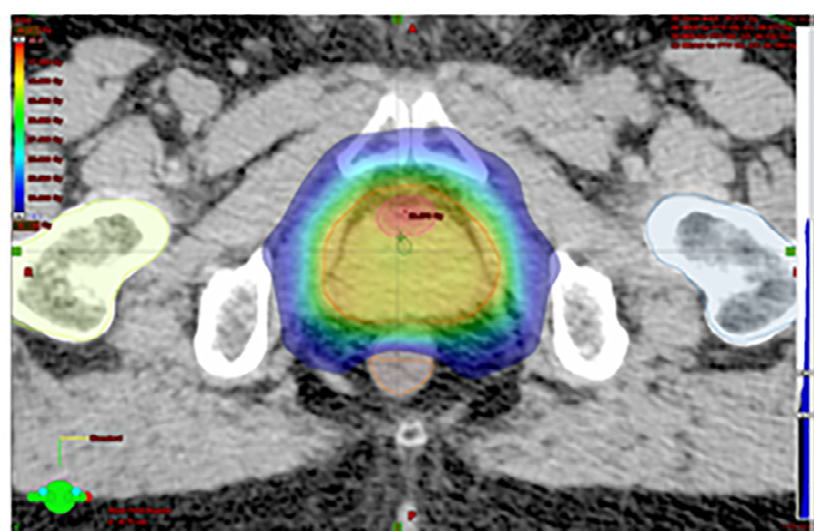

Esempio di piano di cura radioterapico per il trattamento del tumore alla prostata (Mambretti et al. – Radiother Oncol 2018)